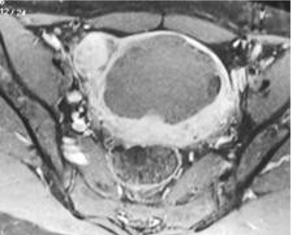

42岁,月经过多伴贫血(Hb 8 g/dL),痛经,腹部膨隆逐渐增加;以前2次怀孕;1堕胎;1活产;未有进一步怀孕计划

弥漫性子宫腺肌症,病变梗死

子宫容积减少

局限性 vs 弥漫性 Focal vs diffuse

深度侵入 Depth of invasion